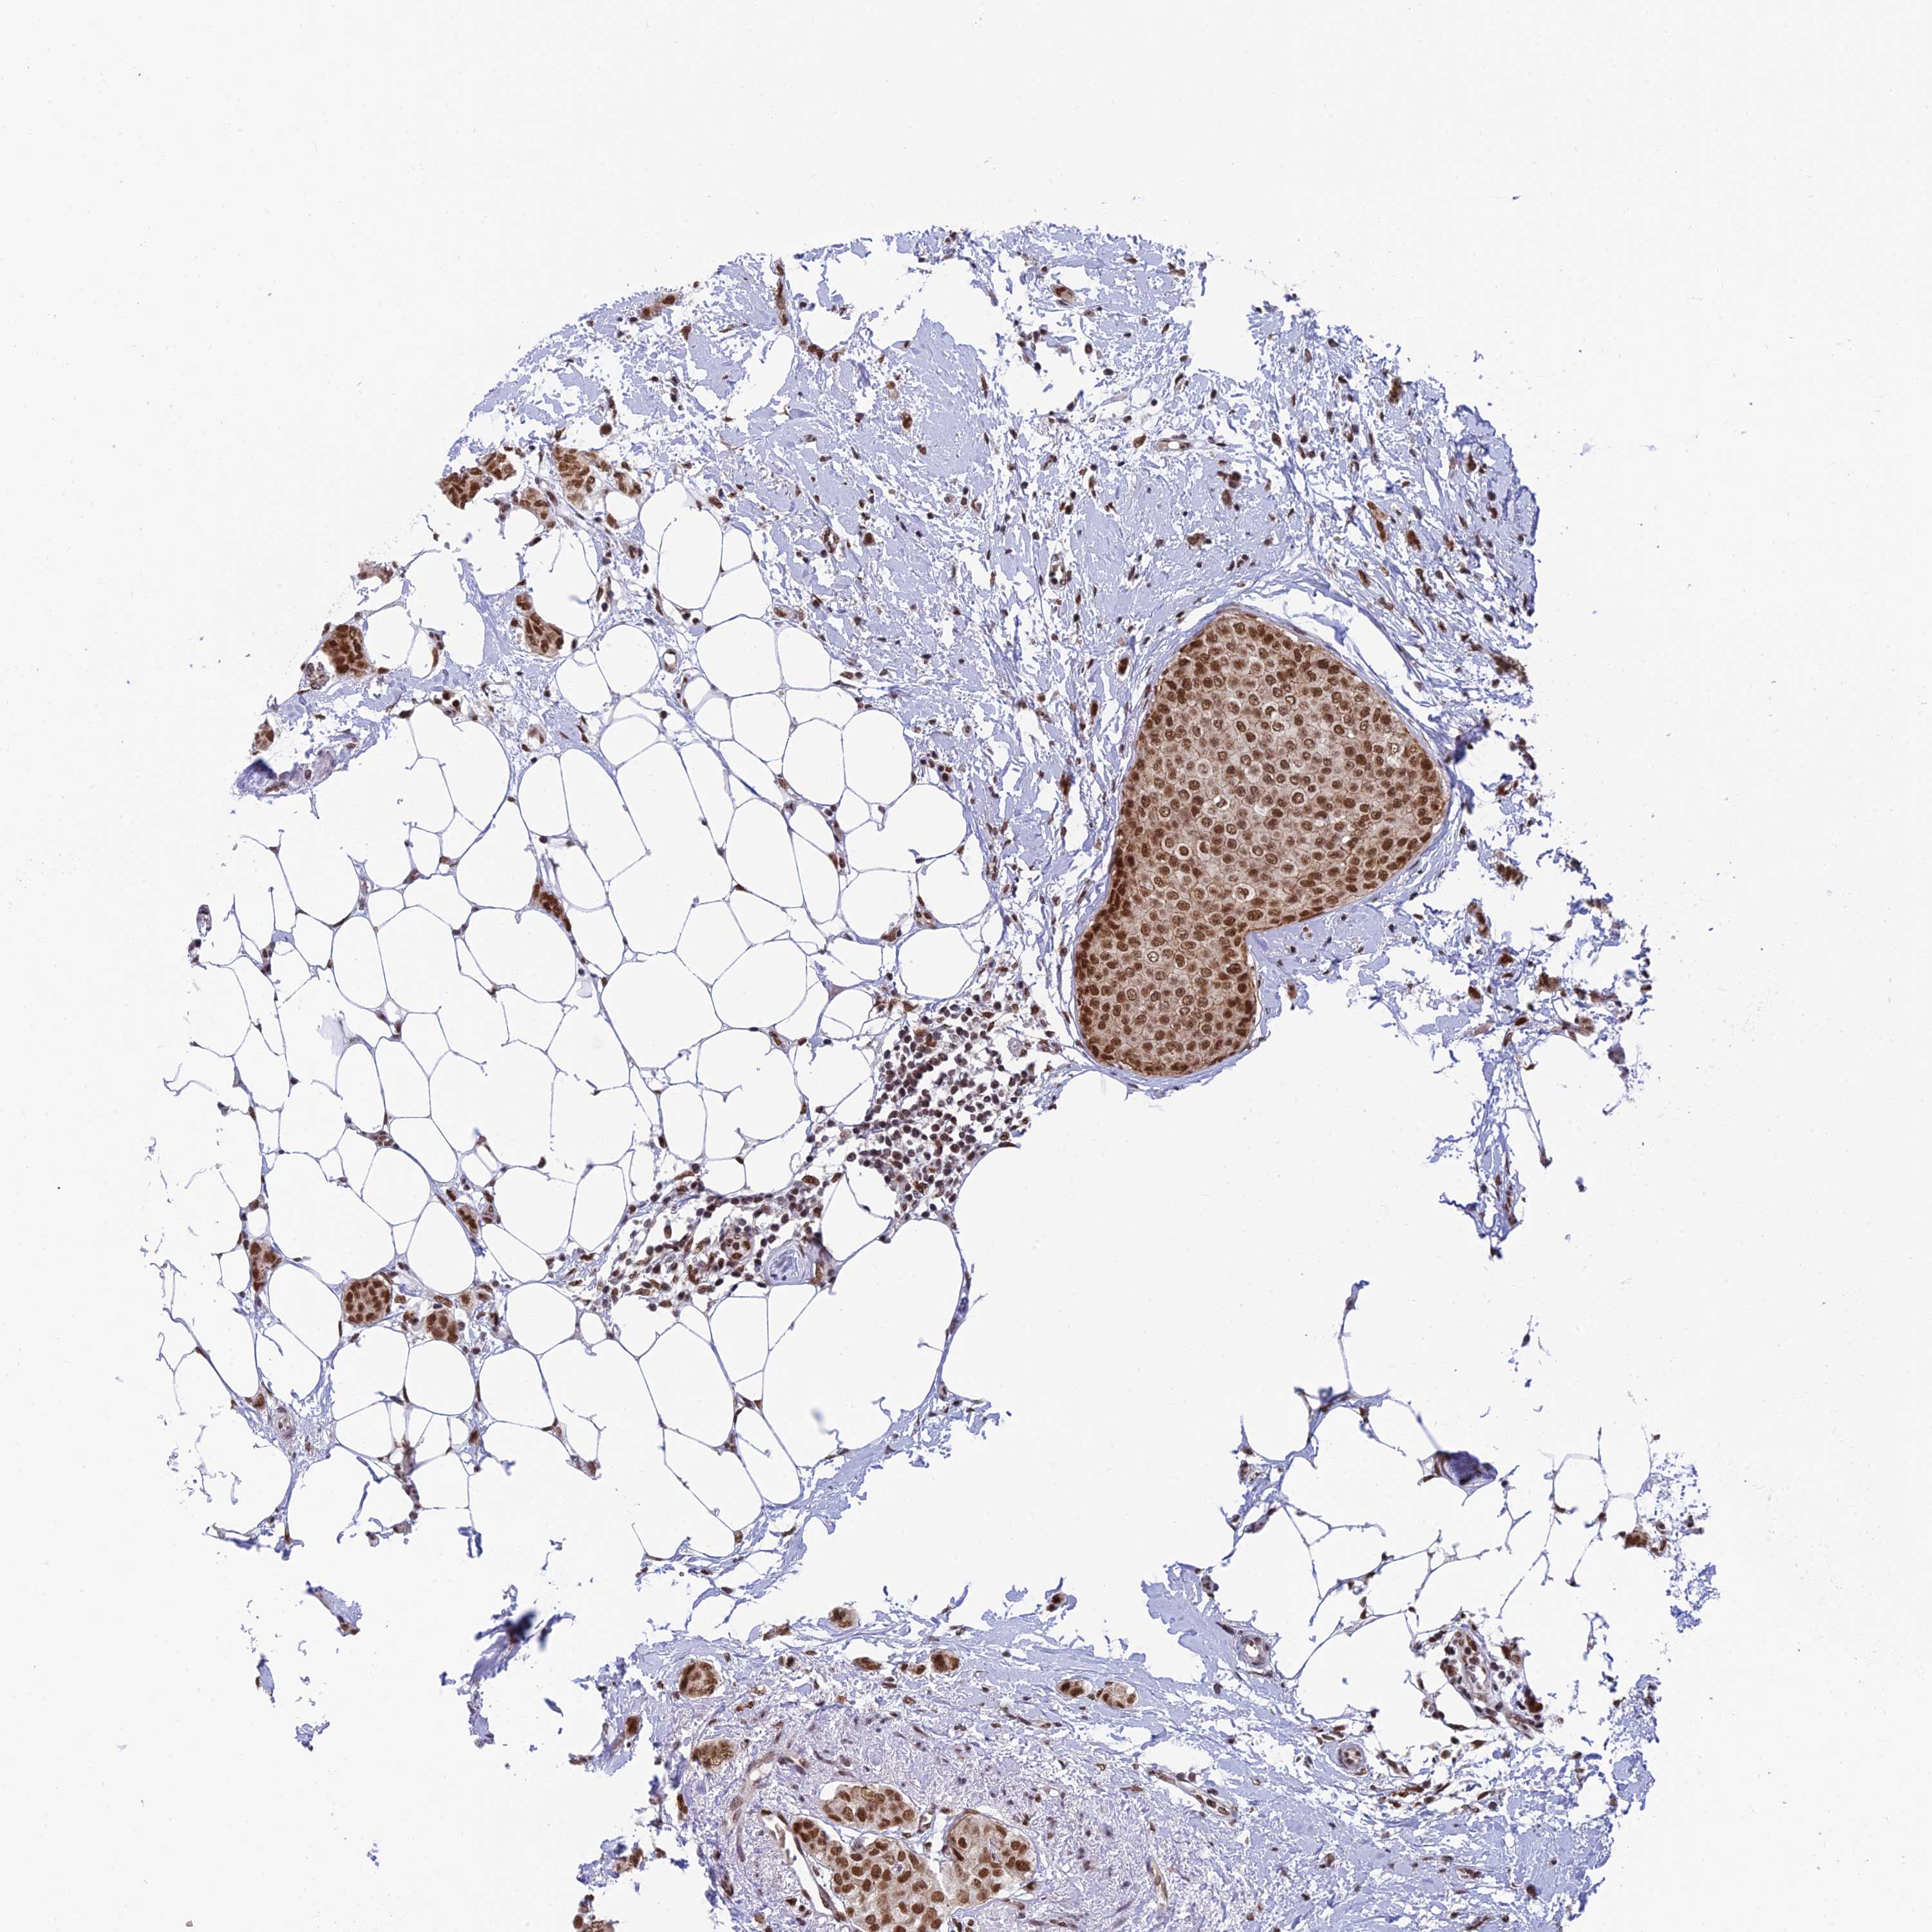

BRCA TCGA BRCA VALIDATION PROTEIN EXPRESSION

ANTIBODIES

AND

VALIDATION